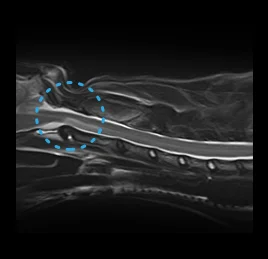

• 허혈성 척수병증

• 척수공동증

• 디스크 탈출증